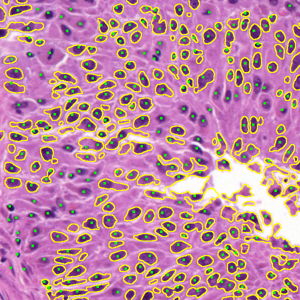

Representative samples from the three datasets are shown in Fig. 1. In (a), the first frame of the synthetic video in Dataset 1 illustrates the strong illumination gradients produced by distance-dependent shading together with orientation-dependent interactions between vertex normals and the light direction. The H&E images in (b) and (c), also from Dataset 1, depict a mast cell infiltrate from a patient with non-alcoholic steatohepatitis and cirrhosis and, respectively, a sample from a patient with sclerosing polycystic adenosis of the parotid gland; the former consists primarily of purple nuclei, white cytoplasm, and pink extracellular tissue. Subfigures (d) and (e) show two examples from Dataset 2 accompanied by their ground-truth nuclei annotations, while (f) and (g) present a representative image from Dataset 3 together with its corresponding cell mask.

Figure 1: Samples from Datasets 1–3. (a) First frame of the 74-frame video in Dataset 1 (1770 × 880) with a superimposed red mesh. (b,c) H&E-stained tissue images from Dataset 1 (1000 × 750; 950 × 730). (d,e) Cell images from Dataset 2 (600 × 600) with nuclei annotations. (f,g) Image from Dataset 3 (512 × 512) with annotation.

Figure 9 shows the segmentation results for the first hematoxylin and eosin (H&E)–stained image from Dataset 1 (see Fig. LABEL:fig_sub:he1_image). Initial level sets and superpixels are shown in Figs. LABEL:fig_sub:he1_in1_zz-LABEL:fig_sub:he1_in_SP: AR and ZZ used two distinct level sets for nuclei (S1) and cytoplasm (S2) (Figs. LABEL:fig_sub:he1_in1_zz-LABEL:fig_sub:he1_in2_zz), while SP and SMST (Fig. LABEL:fig_sub:he1_in_SP) used the same set of 4000 Power-SLIC superpixels in the same color space (red channel for S1, remaining channels for S2). SAM does not allow separate-channel segmentation; its combined S1/S2 result is shown in Fig. LABEL:fig_sub:he1_out_SAM. Figures LABEL:fig_sub:he1_out1_AR-LABEL:fig_sub:he1_out1_SP display S1 results for AR, ZZ, SMST, and SP, and Figs. LABEL:fig_sub:he1_out2_AR-LABEL:fig_sub:he1_out2_SP show the corresponding S2 results.

AR seemed highly sensitive to initialization, segmenting mainly regions near seed points and requiring seeds in nearly all connected foreground components for satisfactory performance. ZZ segmented a wider range of objects from fewer seeds but incorrectly included nuclei in cytoplasm segmentation, failing to capture white regions and introducing spurious tissue. SAM automatically detected many nuclei and some cytoplasm but merged all structures into a single segmentation, limiting its practical utility here. SMST was the fastest but failed to recover large homogeneous regions, such as the background, and frequently fragmented them due to its variance-based metric. In contrast, SP yielded the most accurate results on both S1 and S2, with clear background separation and precise boundary delineation.

Figure 9: Unsupervised segmentation of the image in Fig. LABEL:fig_sub:he1_image for two structures: purple cells (S1) and white cytoplasm (S2). Initializations via level sets (LS) for AR and ZZ are shown in (a, b); 4000 superpixels for SMST and SP in (c) (red channel for S1, remaining channels for S2). SAM does not allow separate-channel segmentation; its overall output is in (d). Results for S1 are in (e–h) and for S2 in (i–l). Computation times (S1/S2, in seconds): AR 829.51/570.32, ZZ 4304.50/4470.56, SMST 0.38/0.38, SP 5.98/4.26; superpixels in (c) computed in 0.17s, SAM in (d) in 7.42s.